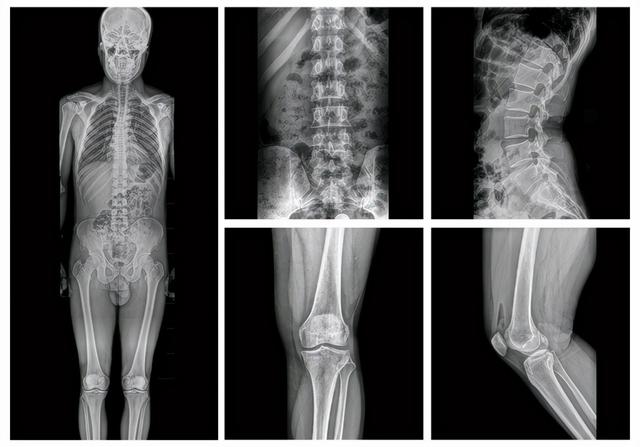

全链AI胸部影像智能分析系统基于基于计算机视觉算法、大数据训练、神经网络的深度学习,将AI融入到放射医学影像全流程中,实现智能检索,海量筛查以及精确诊断,为临床提供更高质量超清影像,并以一致客观的量化标准实现自动化测量、批量数据准确筛查和多类型病灶智能提示功能,有效提升临床诊断质量、效率和收益,强化体检中心在同等规模体检中心的竞争力,减低阅片医生工作负担并优化患者就诊体验。